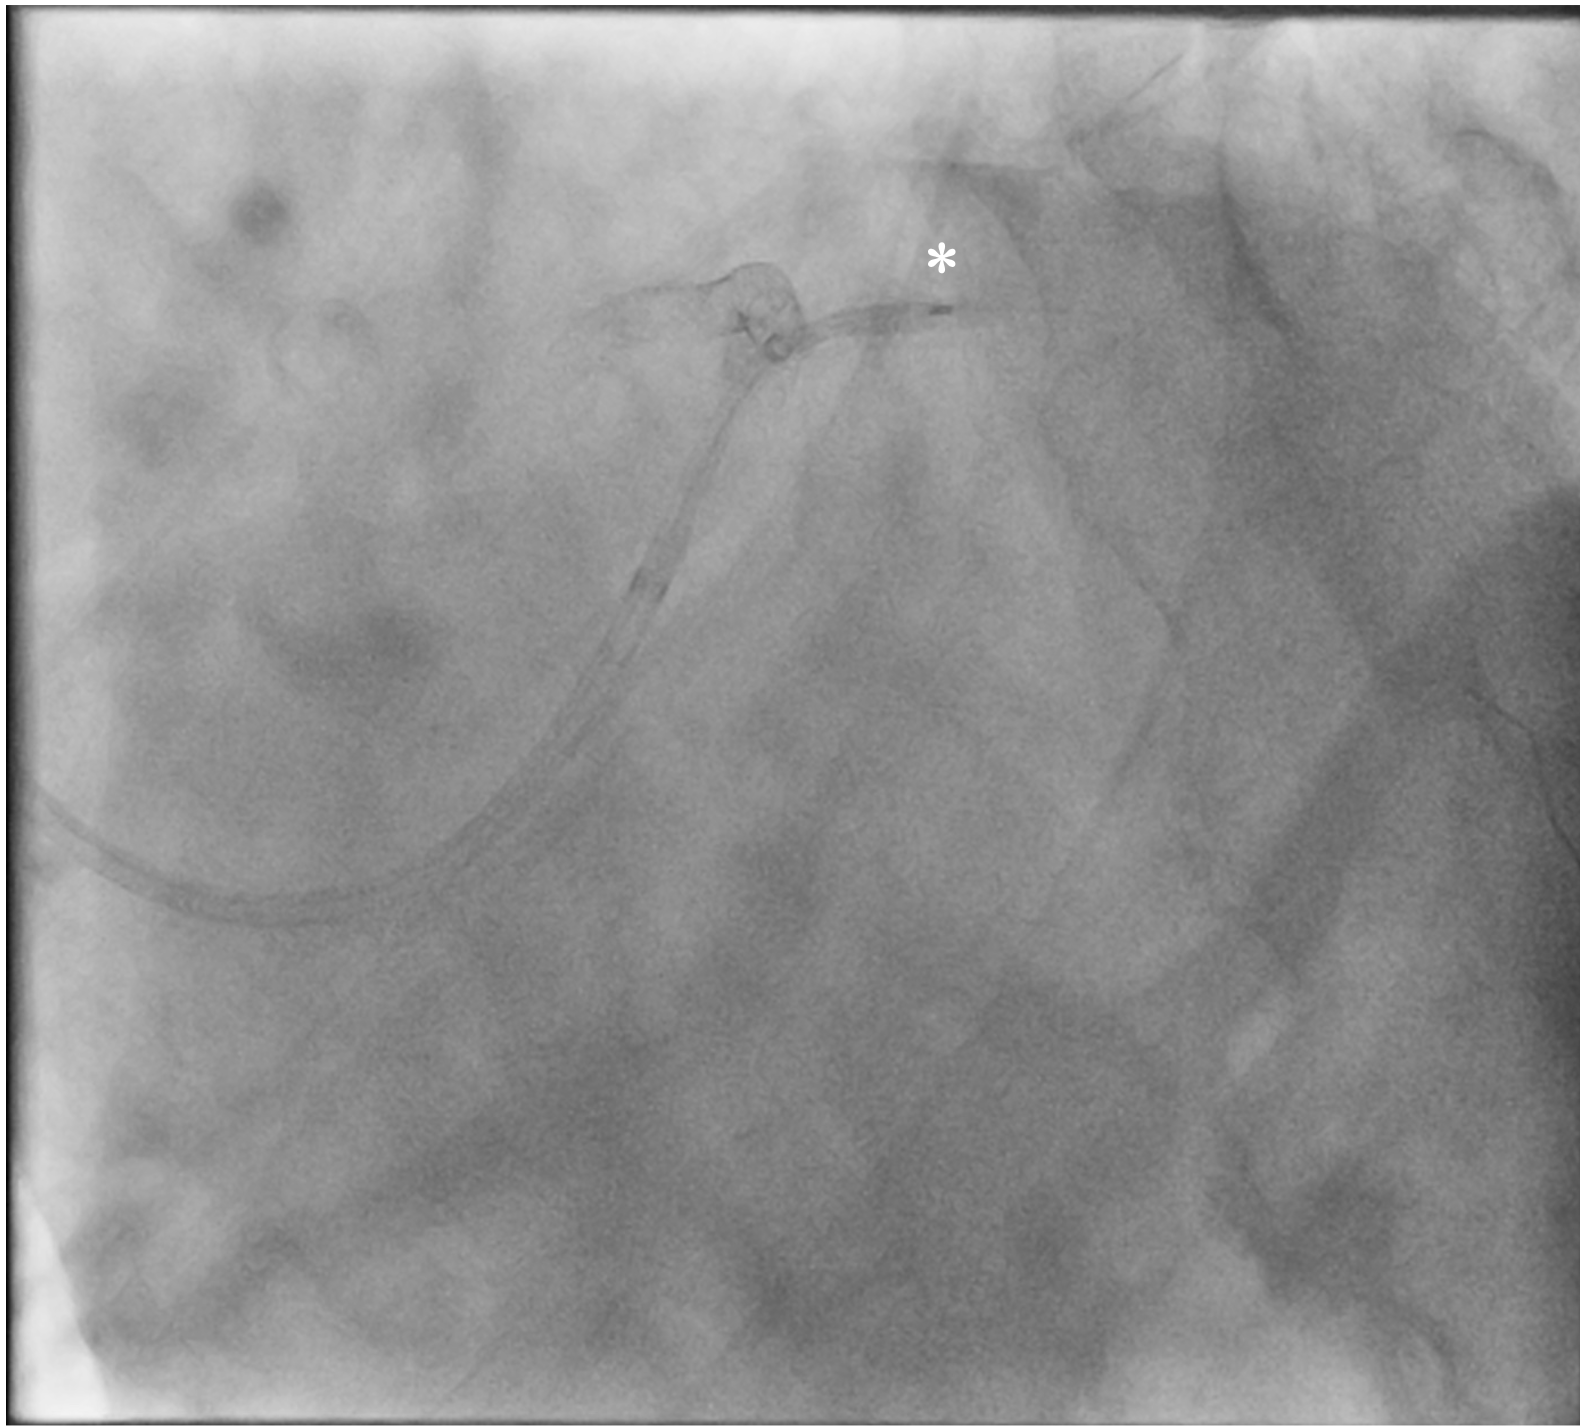

A 71-year-old man who had undergone percutaneous transluminal coronary angioplasty (PTCA) in 2013 was admitted for unstable angina. Coronary angiogram showed 2 de novo lesions at the proximal and distal left circumflex artery (LCX) (Figure 1A). PTCA was performed transradially via a 6-French (Fr) sheath. With a 6-Fr extra-backup 3.5 guide catheter engaging to the left main coronary artery (LM), a 2.5 x 18-mm drug-eluting stent (DES) was delivered to the distal LCX lesion but was inadequate for complete lesion coverage (Figure 1B). During retrieval, the stent was found dislodged at the distal LM bifurcation (Figure 1C).

Distal small balloon retrieval was unsuccessful (Figure 1D). With the help of the Balloon-Assisted Guide-extension (BAG) system, the stent could be optimally positioned at the proximal LCX lesion by forward pushing with a 6-Fr Guideliner V3 catheter (Teleflex) and backward pulling by the small balloon (Figure 1E and F; Video). It was then deployed by sequential balloon dilatation with good expansion (Figure 1G and H). Another 2.5 x 24-mm DES was deployed at the distal LCX, which gave an excellent final angiographic result (Figure 1I and J).